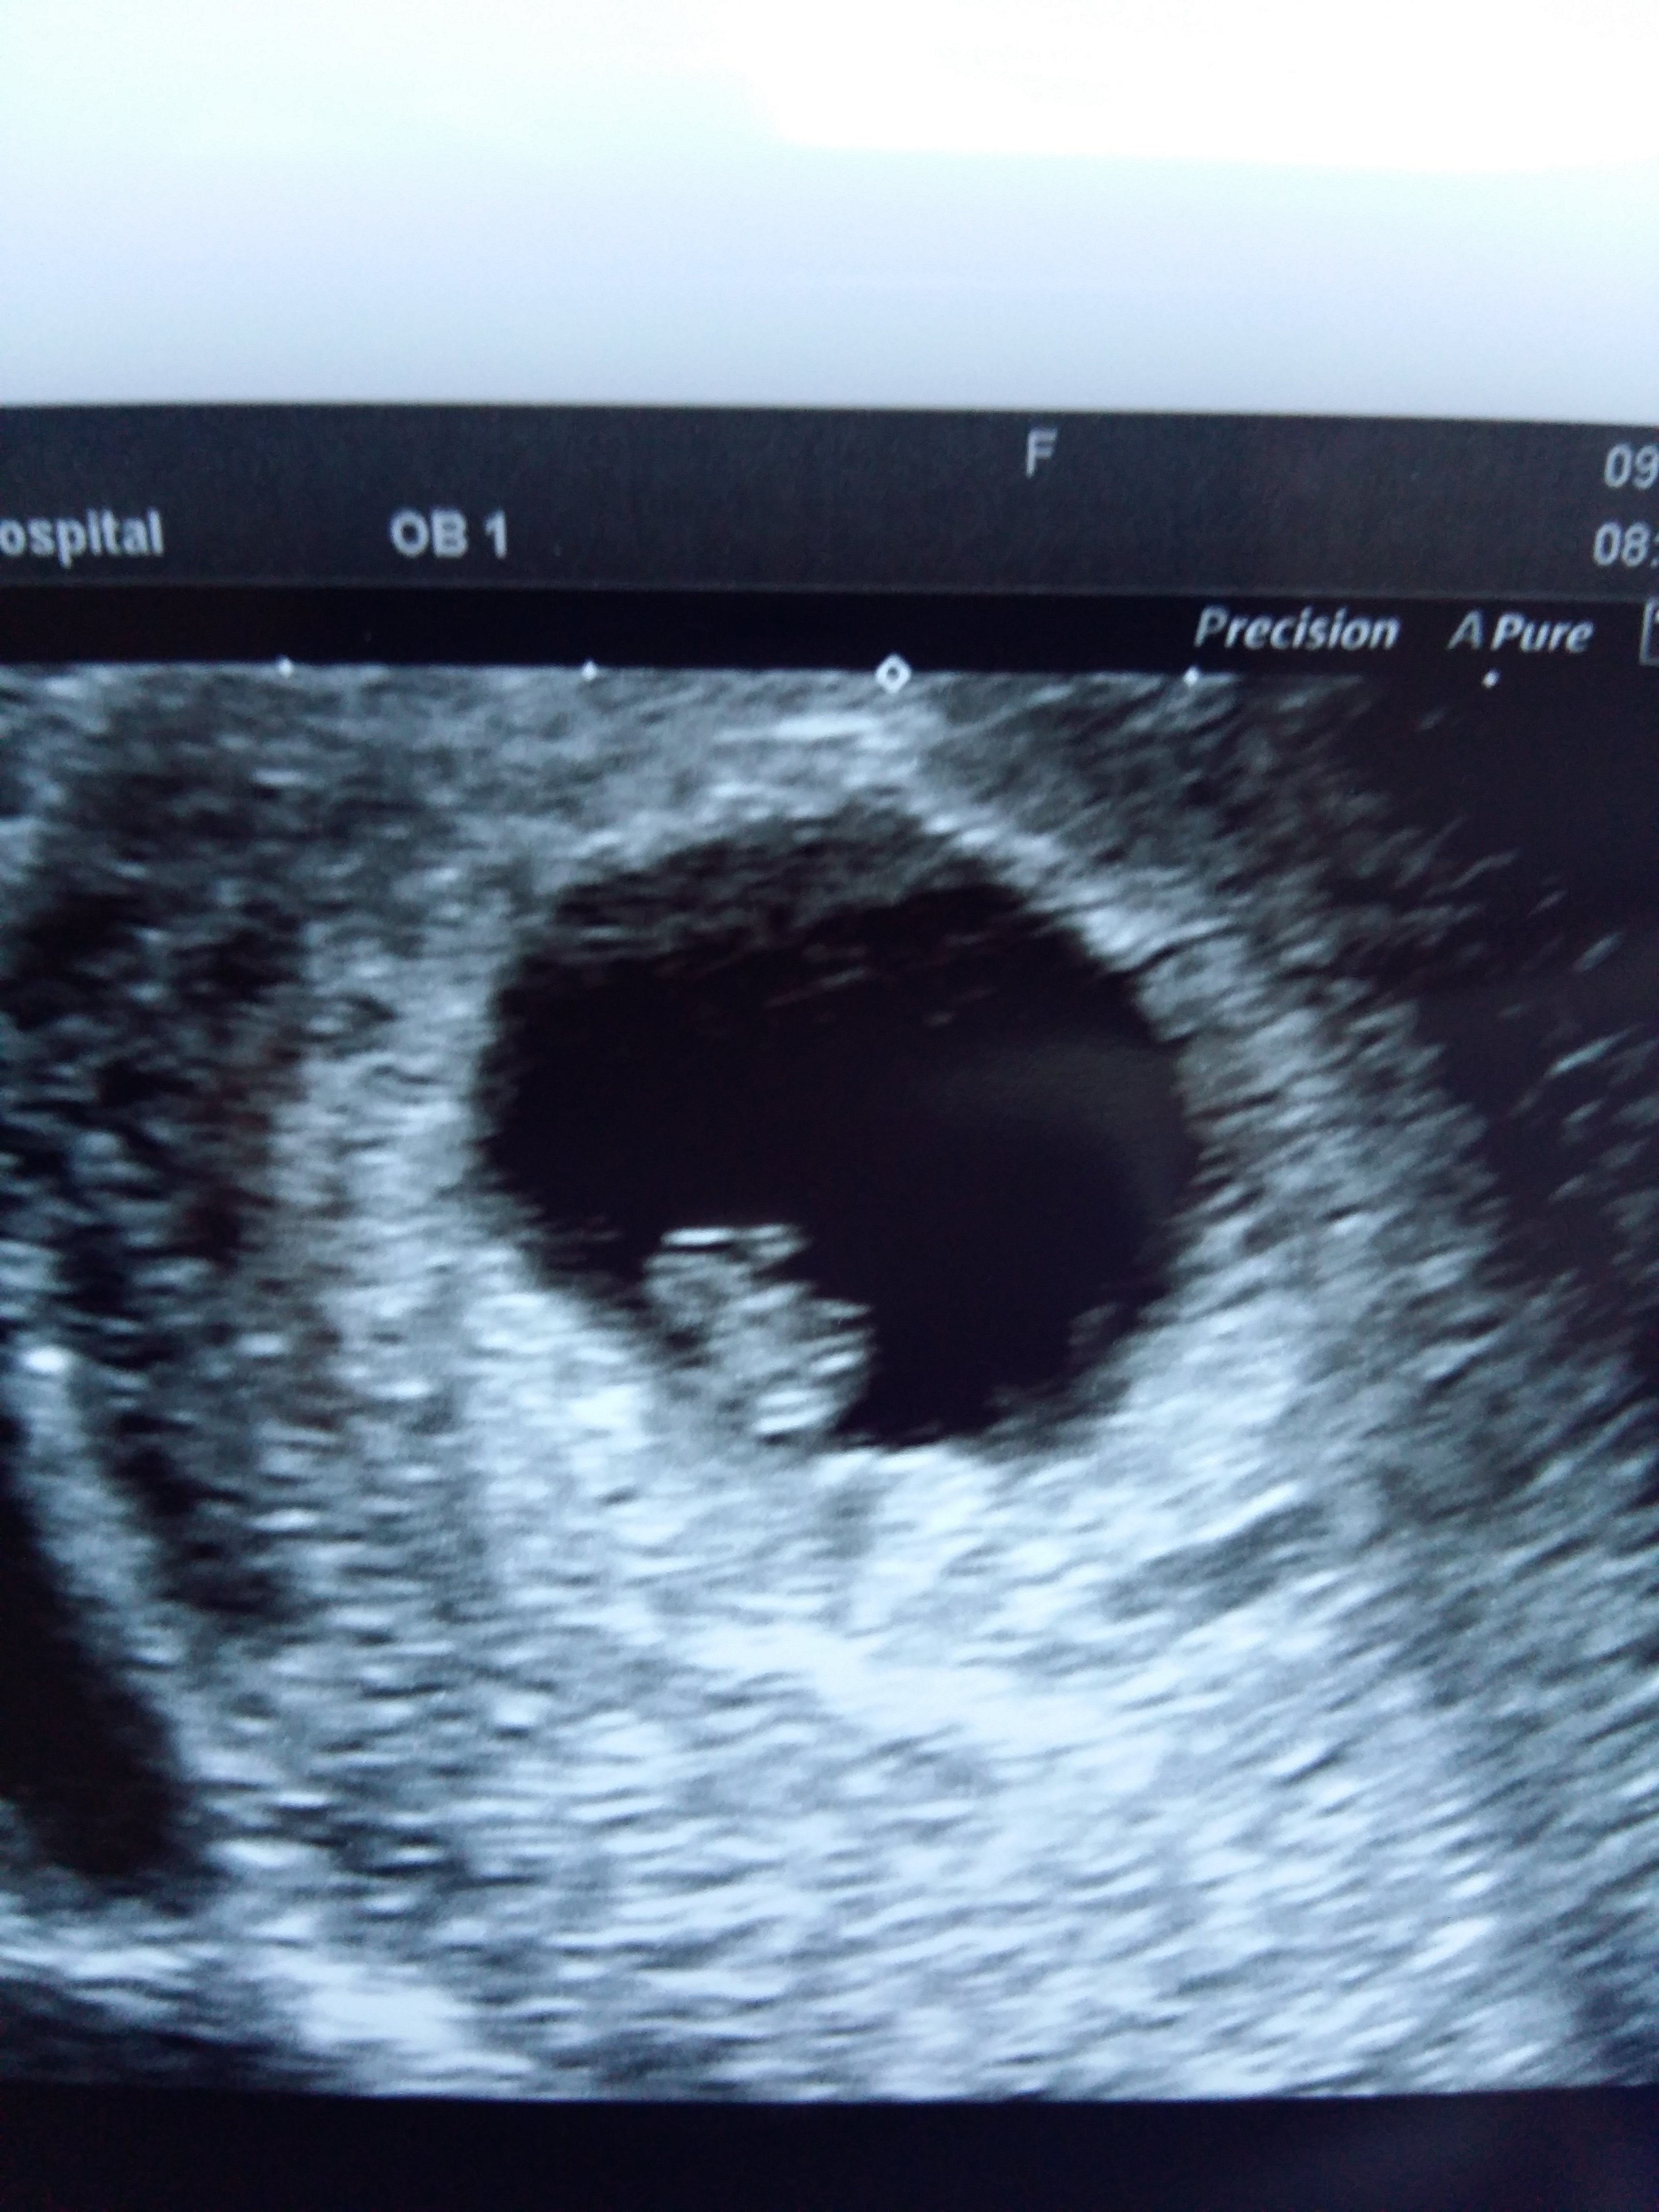

A ja dziś miałam wizytę rano.

Idealnie się zgadza co do dnia z moimi obliczeniami komputer tez obliczył mi na 6t6d dzidzia ma 0.85cm

Usg miałam robione przez powłoki brzuszne babka twierdziła ze tak wszystko widać dobrze ze nie trzeba było się rozbierać .

Ciąża wchlonela polipy znikły ani śladu nie ma suksec 🤗

• 20200309_085334.jpg

20200309_085334.jpg

1,1 MB · Wyświetleń: 98